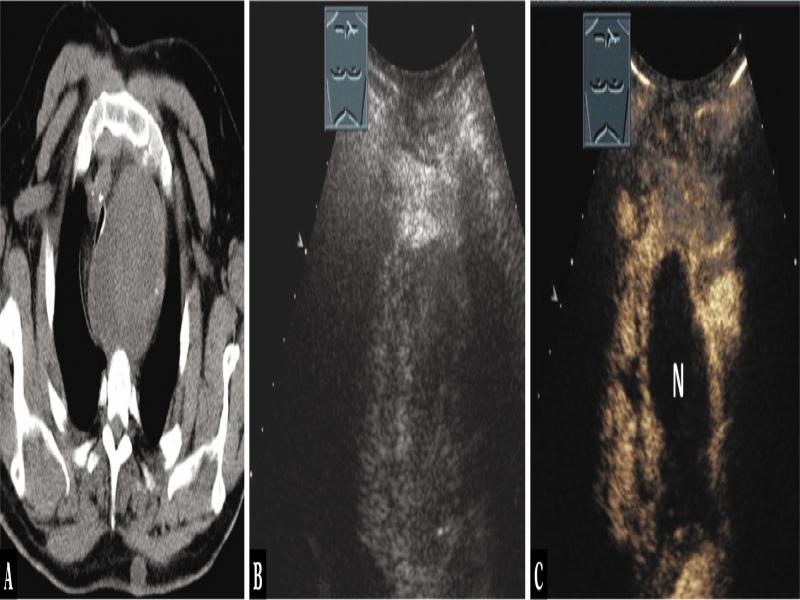

Fig. 1.

A 40-year-old female patient with mediastinal tumor in the anterior mediastinum as an incidental finding in computed tomography (A). Thoracic ultrasound indicated anechoic nodes (B), which showed no enhancement on contrast-enhanced ultrasound (C). Mediastinoscopy was performed, and regressive thymoma was histologically confirmed